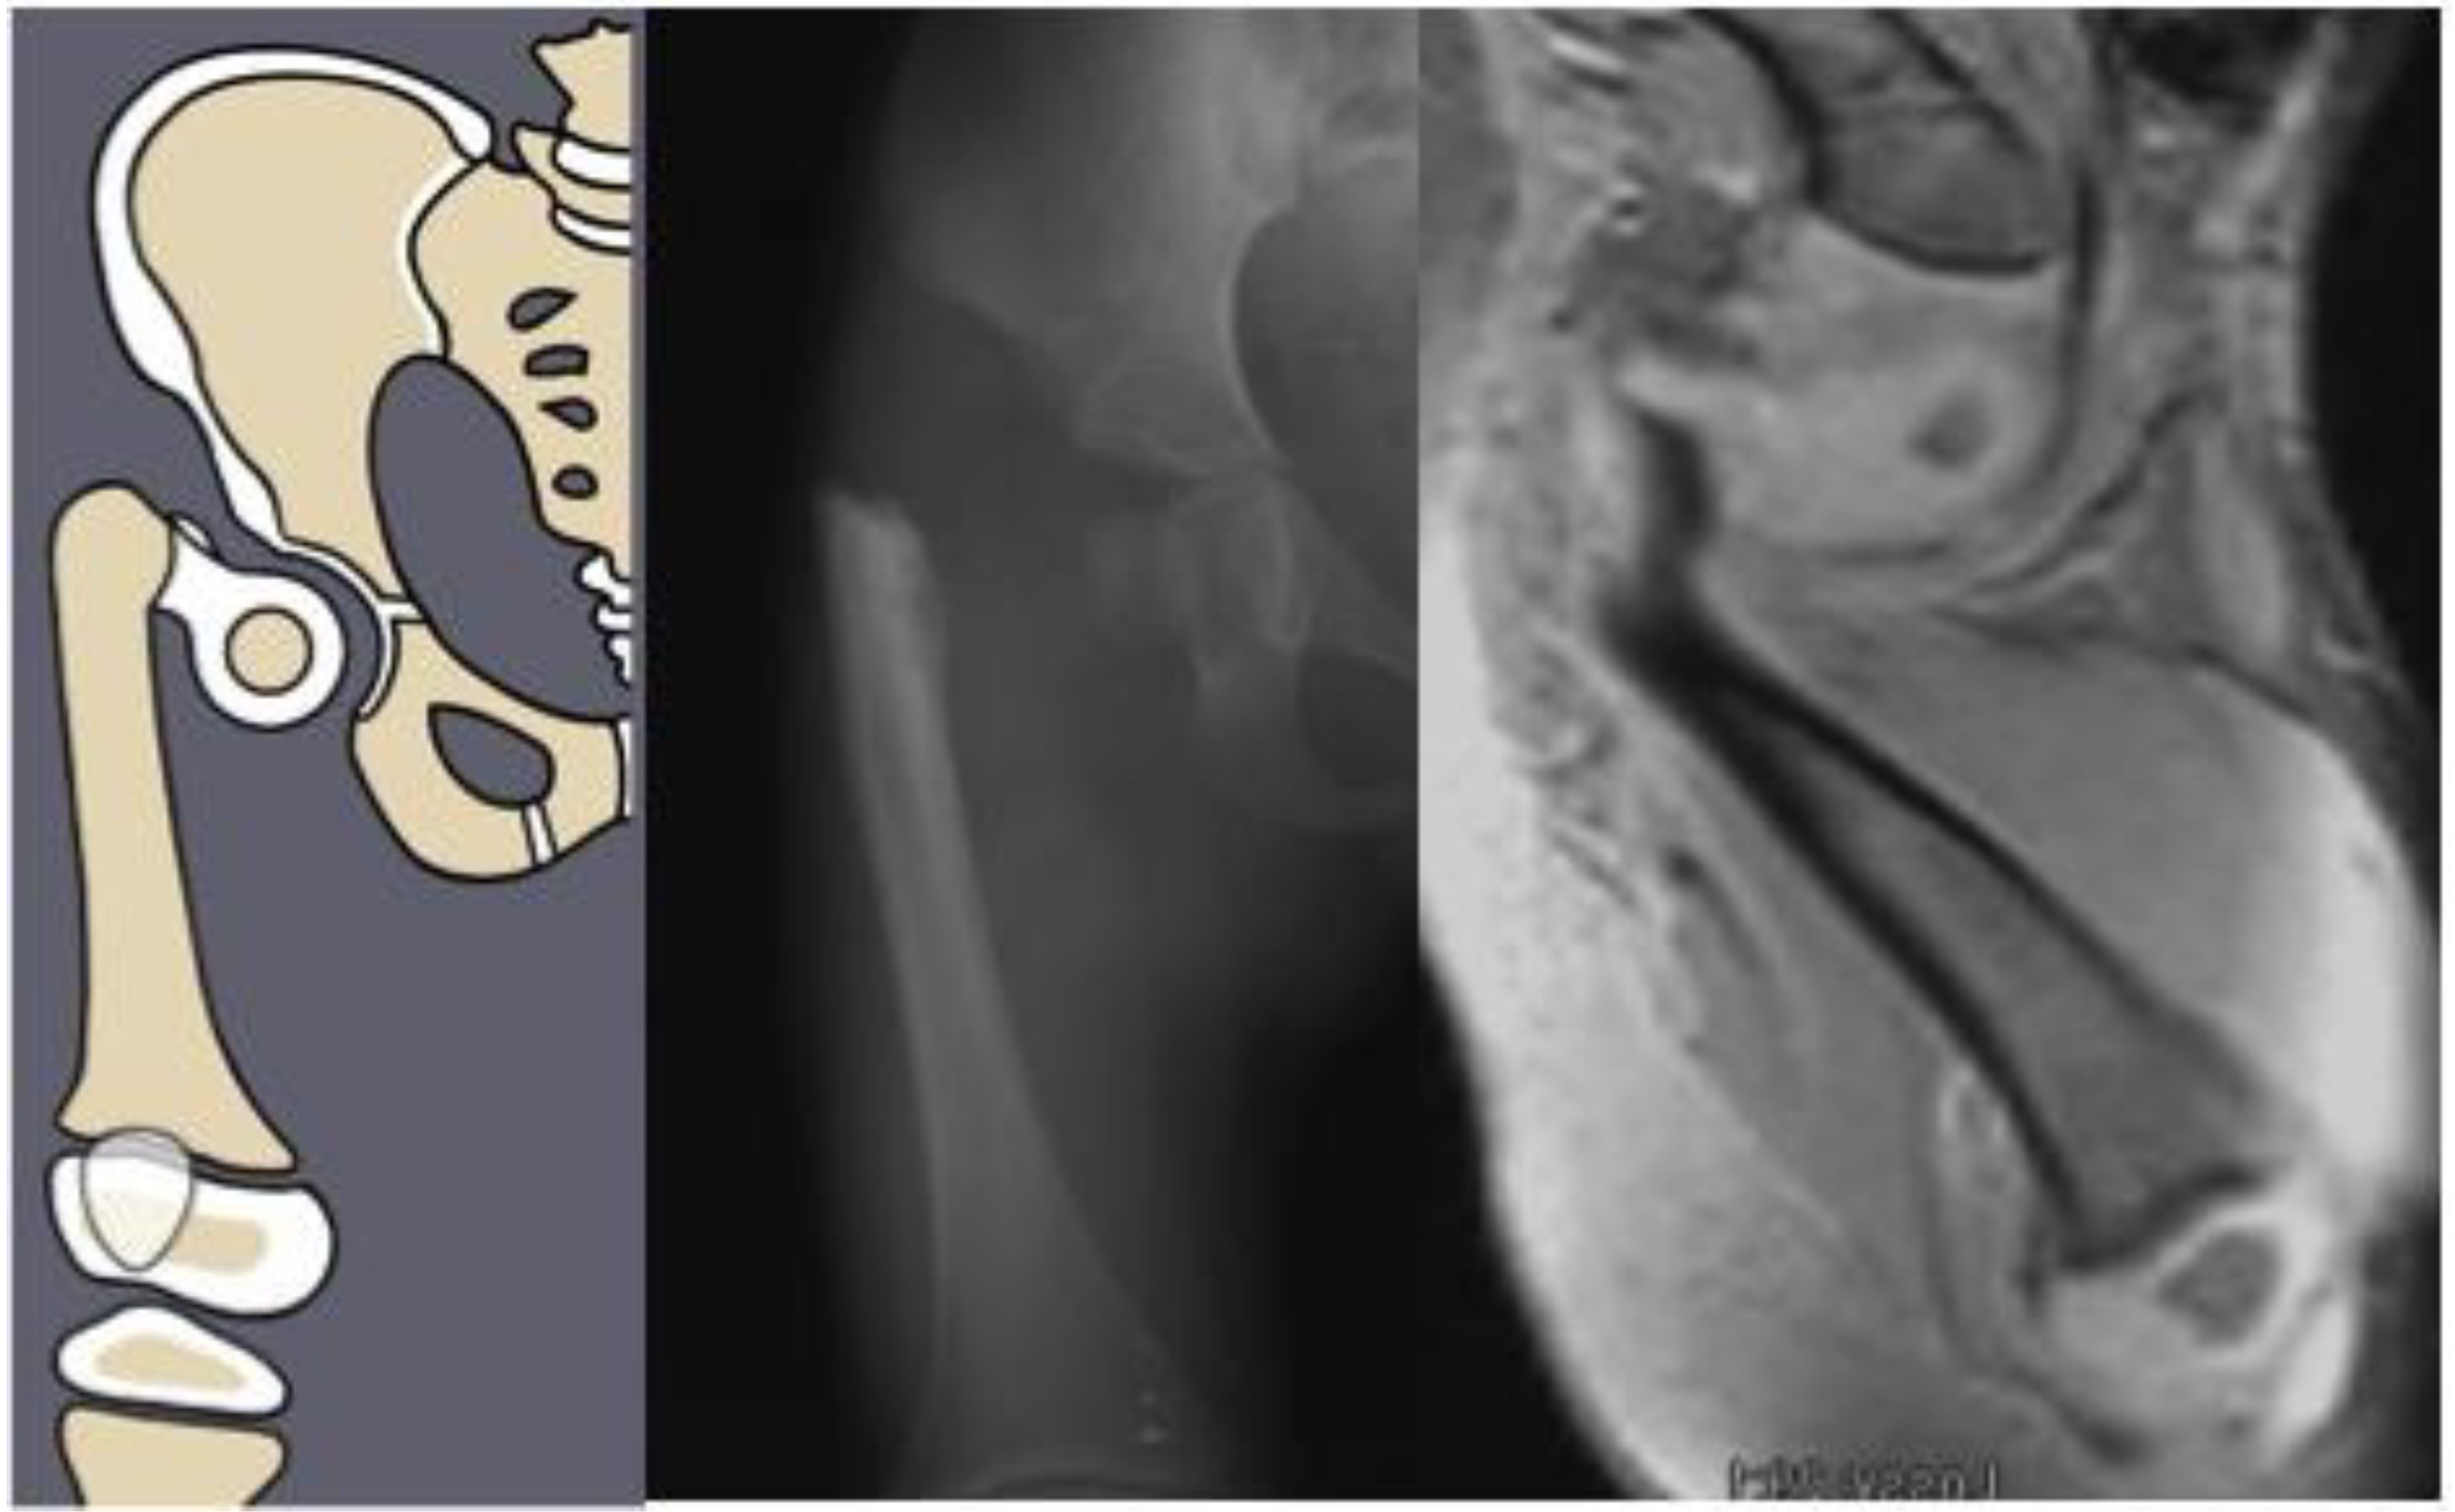

Figure 2.

Paley type 1b2 (neck type) CFD example. Illustration (left), radiograph showing delayed ossification of femoral neck (center), and MRI showing cartilaginous neck (right).